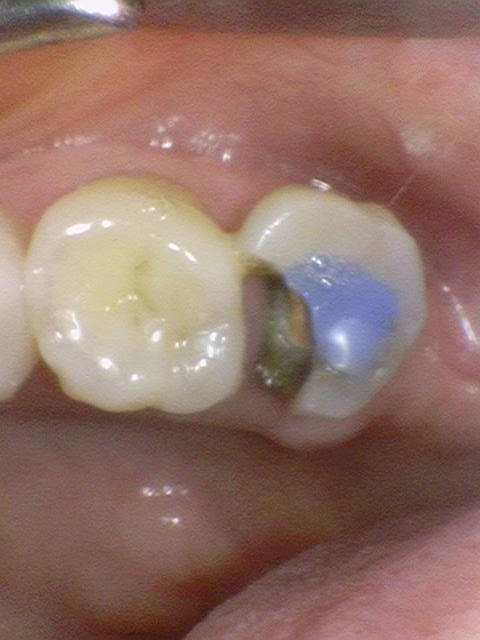

아래 사례와 사진은 실제 저희 연세예감치과 환자의 사례와 치아 사진으로

환자분의 동의를 얻은 사진만 게시합니다.

충치가 심한 치아를 크라운(지르코니아 크라운)으로 해서 자연스럽게 만든 모습. 시청역치과